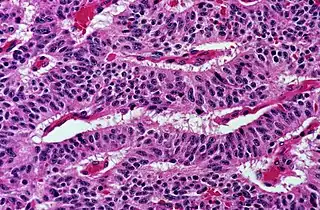

.jpg.webp)

Studies have shown that once a human reaches adulthood, bone density steadily decreases with age, to which loss of trabecular bone mass is a partial contributor.[8] Loss of bone mass is defined by the World Health Organization as osteopenia if bone mineral density (BMD) is one standard deviation below mean BMD in young adults, and is defined as osteoporosis if it is more than 2.5 standard deviations below the mean.[9] A low bone density greatly increases risk for stress fracture, which can occur without warning.[10] The resulting low-impact fractures from osteoporosis most commonly occur in the upper femur, which consists of 25-50% trabecular bone depending on the region, in the vertebrae, which are about 90% trabecular, or in the wrist.[11]

When trabecular bone volume decreases, its original plate-and-rod structure is disturbed; plate-like structures are converted to rod-like structures and pre-existing rod-like structures thin until they disconnect and resorb into the body.[11] Changes in trabecular bone are typically gender-specific, with the most notable differences in bone mass and trabecular microstructure occurring within the age range for menopause.[8] Trabeculae degradation over time causes a decrease in bone strength that is disproportionately large in comparison to volume of trabecular bone loss, leaving the remaining bone vulnerable to fracture.[11]